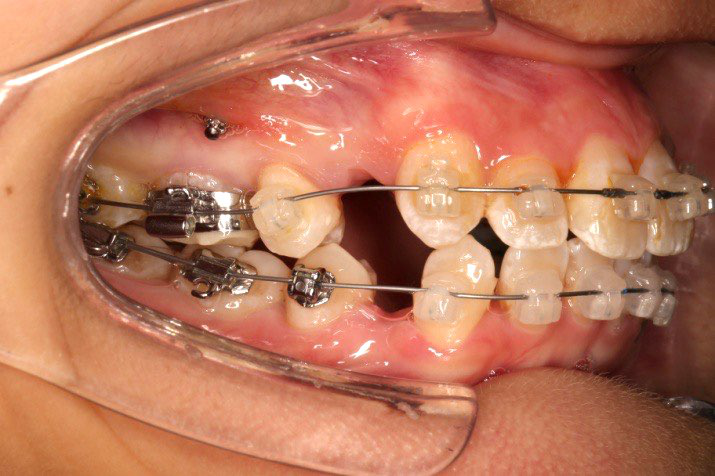

2016.10.31  初戴,0.013cu-niti2017.1.13  上颌加TPA,U56间斜形植入韩国庆北1312-08种植钉,上下0.16cu-niti

2017.02.16  上下0.014*25 cu-niti,50g 拉尖牙远中

2017.04.28

2017.04.28  上0.016*25ss 13、23近远中约5度 v形曲,下0.017*25ss

2017.05.26  磨牙近中倾斜,下颌36、46加power arm